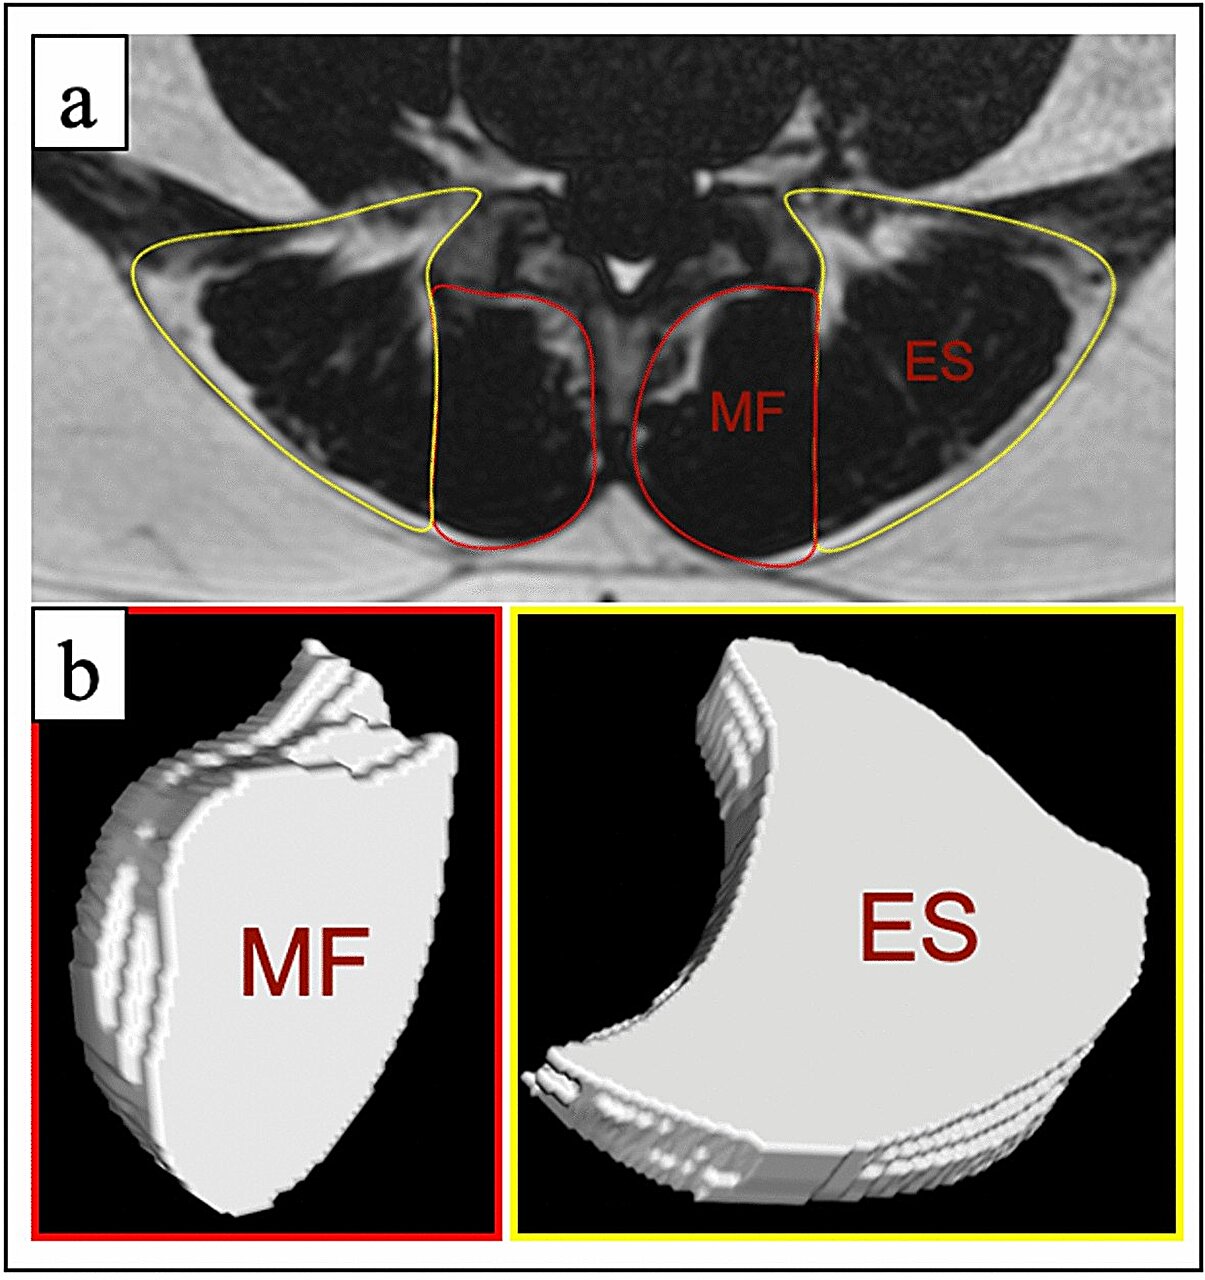

Participants in the aquatic group didn’t just get stronger—they got emotionally lighter. They reported reduced levels of pain-related fear, less catastrophic thinking, and significant improvements in sleep quality. While both groups gained lumbar strength, only the aquatic group showed marked increases in specific upper spinal muscles—the multifidus and erector spinae—that are critical for posture and spinal support.